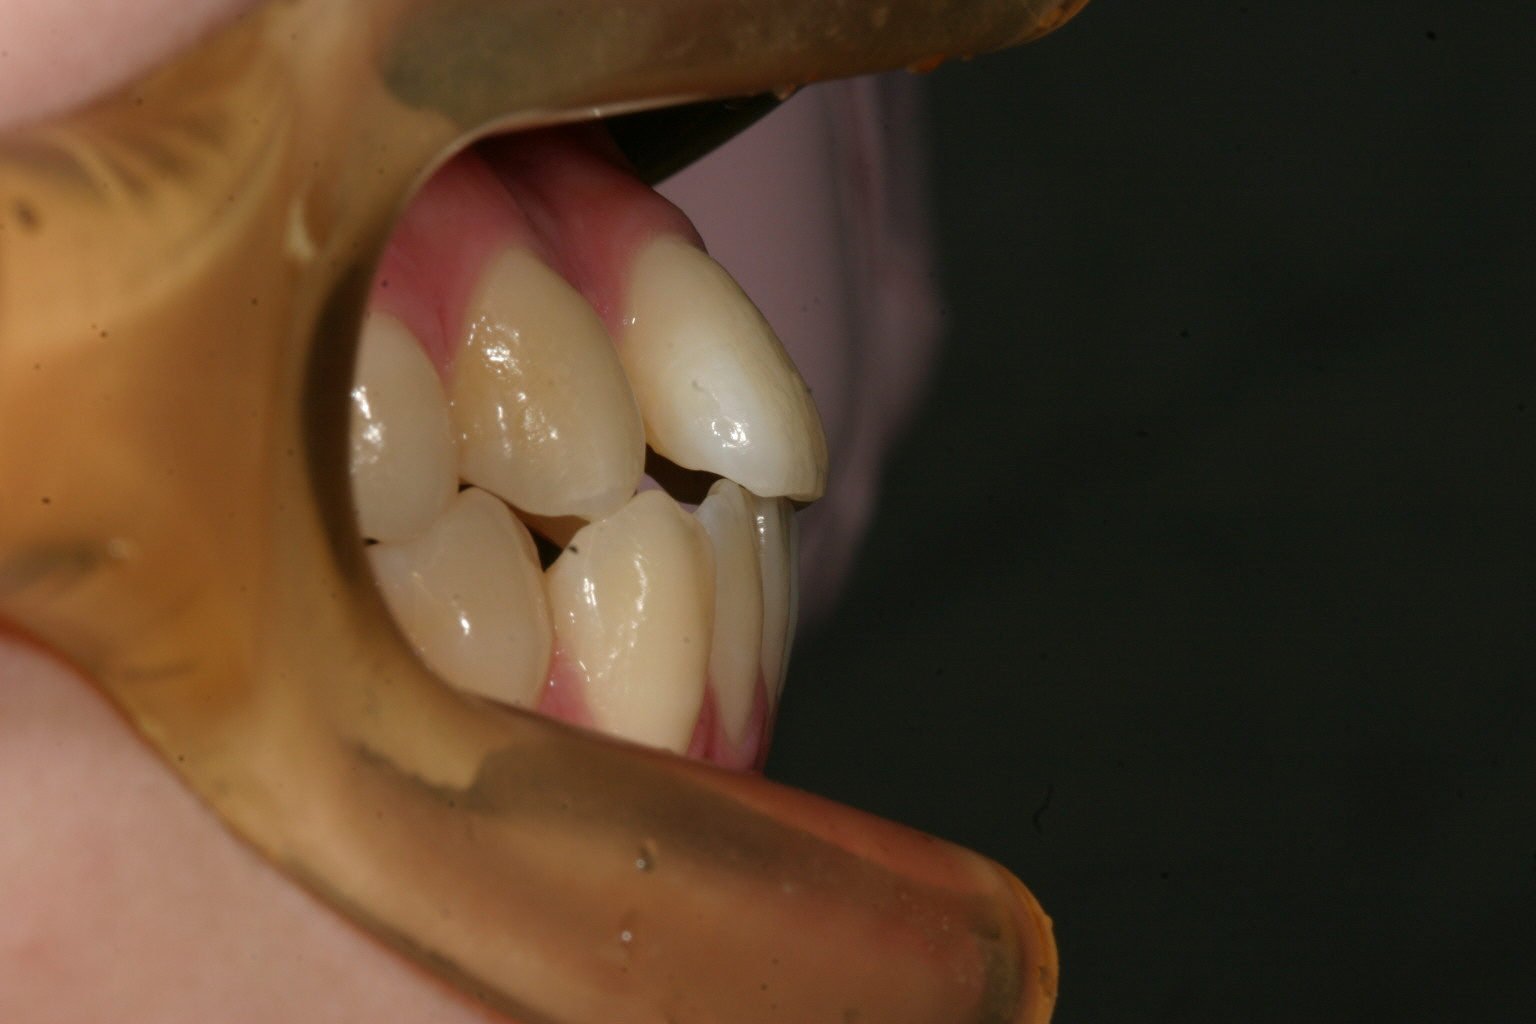

少し出っ歯感があります。

今回のケースは極度な前歯の飛び出しによる叢生改善です。

やはりいつも言っているのですが叢生になる原因はたいていの場合アーチフォームの前歯部が狭い為に前歯が並ばないと言う事です。

この様な場合アーチフォームのU字型に改善するのとIPR(歯と歯の間を削る)による事で、でっぱ改善を行います。